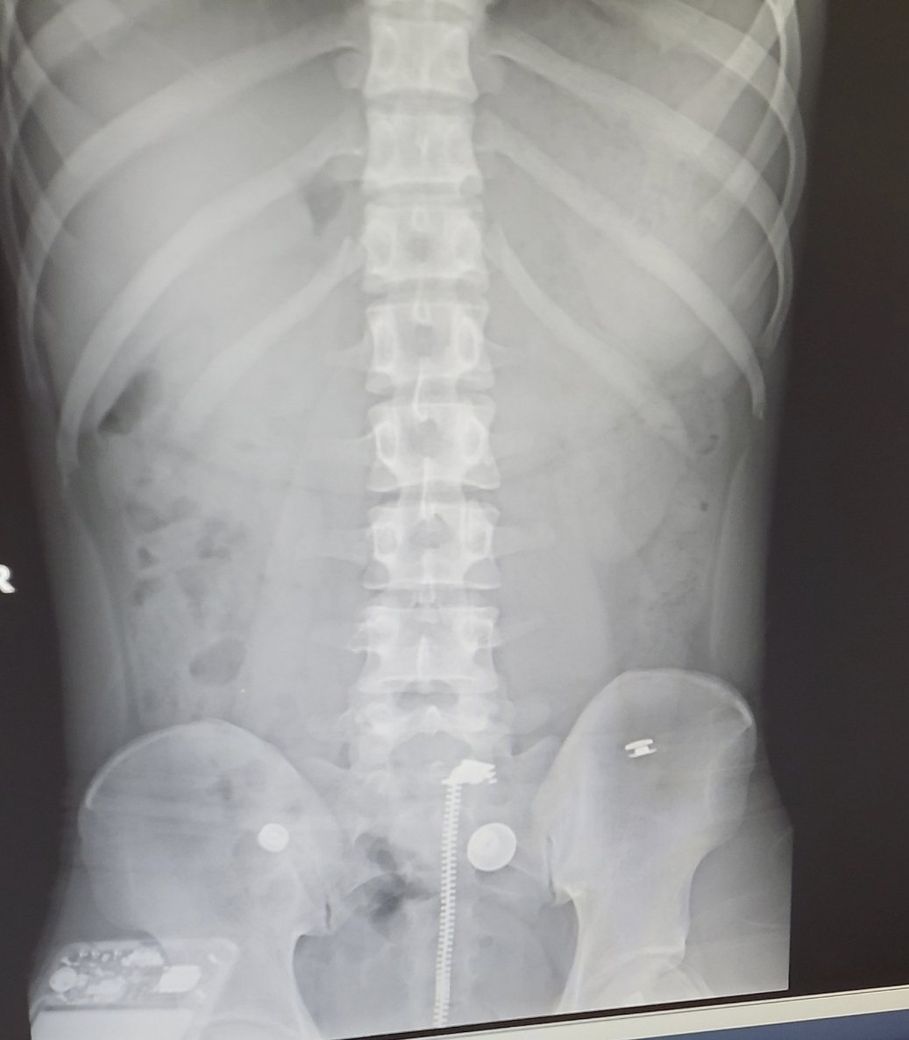

제 골반이 어떻게 틀어졌는지 궁금합니다

제 엑스레이 사진입니다

현재 몸 상태가 왼쪽이 전반적으로 불편해서

병원가서 엑스레이를 찍어봤더니

제 몸을 기준으로 왼쪽 골반이

올라가 있는 상태라고 들었습니다

근데 제가 궁금한건 오른쪽 골반과 비교했을때

왼쪽 골반의 모양이 많이 달라서 단순히 높낮이의 차이 말고

골반이 어떤식으로 틀어진건지 궁금해서 여쭤봅니다.

현재 2차원적인 엑스레이만으로는 단순히 좌측 골반이 올라가 있는 것외에는 골반이 어떻게 뒤틀려져 있는지 파악하기 어렵습니다. 촬영한 곳의 담당 의사에게 진료를 보신 후 의견을 구하는 것이 좋겠습니다.

유감스럽지만 올리신 엑스레이 사진으로는 전면-후면의 골반 상태만 파악할 수 있으며, 해당 사진으로는 골반의 좌측이 우측보다 많이 올라가 있고 틀어져 있다 정도의 소견만 볼 수 있습니다. 구체적으로 어떻게 틀어졌는지 파악하기 위해서는 입체적으로 여러 각도에서 엑스레이 사진을 찍어보거나 CT 검사가 필요하겠습니다.

비스듬하게 촬영된 사진 1컷만으로는 정확한 확인이 불가능합니다.

또한 상기 사진은 골반이 전반적으로 다 나오지 않은 높이의 사진입니다.

현재 상태로 알 수 있는 정보는 왼쪽 골반이 높이가 높고 앞쪽으로 전진되는 방향으로 뒤틀려 있는 것으로 확인됩니다.

척추측만증같은건 없어보여서 골반자체나 하지길이에 문제가 있을때도 골반이 틀려보일수도 있습니다.